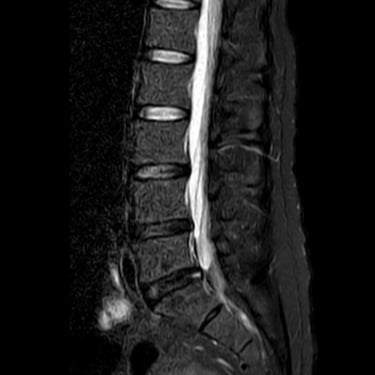

Discopatía Lumbar Degenerativa con Artrosis Facetaria | Diagnóstico por Resonancia Magnética

La discopatía lumbar degenerativa con artrosis facetaria es una causa frecuente de dolor lumbar crónico, que limita la movilidad y la calidad de vida del paciente. Esta condición combina la degeneración de los discos intervertebrales con el desgaste de las articulaciones facetarias, lo que puede generar inestabilidad y compresión nerviosa. La resonancia magnética (RMN) es la herramienta diagnóstica más precisa, ya que permite identificar deshidratación y colapso discal, hipertrofia facetaria, estenosis foraminal y signos de inflamación. El diagnóstico temprano es fundamental para establecer un tratamiento adecuado, que puede ir desde medidas conservadoras hasta técnicas quirúrgicas mínimamente invasivas.